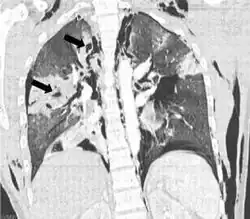

Coronal CT scan showing lucencies (pale areas in radiography) in the lung caused by pulmonary lacerations on the left of the image (black arrows) | |

Pulmonary laceration may not be visible using chest X-ray because an associated pulmonary contusion or hemorrhage may mask it.[1][9] As the lung contusion clears (usually within two to four days), lacerations begin to become visible on chest X-ray.[3] CT scanning is more sensitive and better at detecting pulmonary laceration than X-rays are,[1][5][12][15] and often reveals multiple lacerations in cases where chest X-ray showed only a contusion.[12] Before CT scanning was widely available, pulmonary laceration was considered unusual because it was not common to find with X-ray alone.[12] On a CT scan, pulmonary lacerations show up in a contused area of the lung,[9] typically appearing as cavities filled with air or fluid[16] that usually have a round or ovoid shape due to the lung's elasticity.[4]